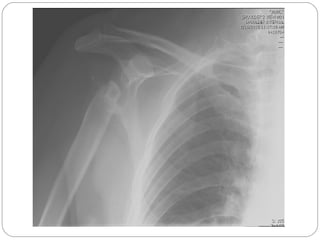

Radiograph

revealed

horizontal

fracture of the

lower patalla